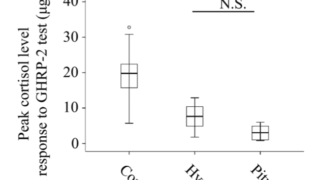

負荷試験でこれらのホルモンの反応が悪い。